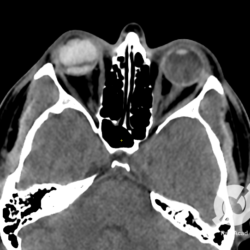

Se a gente for pensar bem, o principal problema do diabetes mellitus é o comprometimento dos pequenos vasos, onde quer que seja, mas obviamente as calcificações coronarianas e cerebrais são as mais preocupantes. Temos aqui uma ressonância magnética na sequência Flair de um paciente diabético de 56 anos, mostrando imagens hiperintensas (branquinhas) periventriculares e na substância branca profunda supratentorial, que correspondem a sequelas de diminutas isquemias que o paciente teve ao longo da vida. Estas lesões são frequentes em pacientes hipertensos e de mais idade, mas não na faixa etária do nosso paciente e muito provavelmente estão pela condição de diabético do paciente.